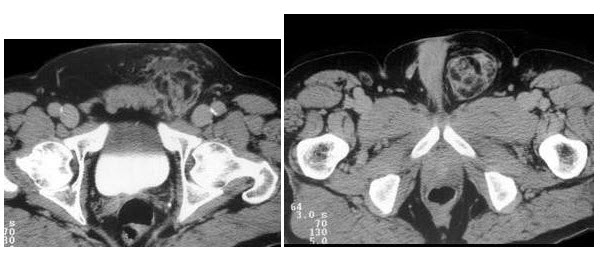

16、多项选择题

男,65岁,左侧腰背部胀痛伴无痛性全程血尿3月余,CT平扫及增强检查如图所示,下列说法正确的是()

A.平扫时见左肾上极有一软组织肿块影,其边界较清楚

B.增强扫描肾皮质期可见肿块明显强化,其内亦有无强化区

C.增强扫描肾实质期可见肿块强化迅速下降,但密度比平扫时仍要高

D.考虑为左侧肾癌

E.考虑为左侧肾错构瘤

点击查看答案

本题答案:微信扫下方二维码即可打包下载完整带答案解析版《★放射医学(医学高级)》或《放射医学(医学高级):CT》题库